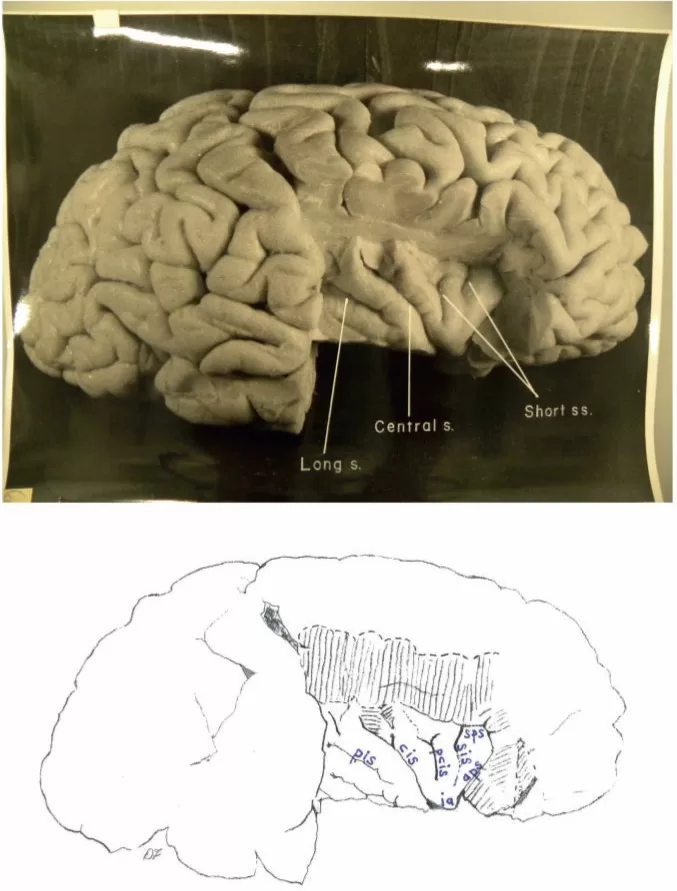

Top: Dorsal photograph of Einstein’s brain with original labels. Bottom: Our identifications. a2 = angular; a3 = anterior occipital; c = central; e = processus acuminis; fm = midfrontal; fs = superior frontal; inp = intermediate posterior parietal; ip = intraparietal; m = marginal; mf = medial frontal; ocs = superior occipital; otr = transverse occipital; par = paroccipital; pci = precentral inferior; pcs = precentral superior; pma = marginal precentral; pme = medial precentral; po = parieto-occipital; prc = paracentral; ps = superior parietal; pst = transverse parietal; pti = postcentral inferior; pts = postcentral superior; rc = retrocalcarine; u = unnamed. k = presumed motor cortex for right hand; K = ‘knob’ representing motor cortex for left hand. In both hemispheres, e limits anteriorly the first annectant gyrus, a pli de passage of Gratiolet that connects the parietal and occipital lobes, indicated by red arrows (see also Fig. 7). This figure is reproduced with permission from the National Museum of Health and Medicine.Top: Photographs of the left (L) and right (R) lateral surfaces of Einstein’s brain taken with the front of the brain rotated toward the viewer, with original labels. Bottom: Our identifications. Numbers 1–4 indicate four gyri in Einstein’s right frontal lobe, rather than three as is typical; K = ‘knob’ representing motor cortex for left hand. Submerged gyri are shaded red near the diagonal sulcus on each side. It is clear from the left hemisphere that the posterior ascending limb of the Sylvian fissure and the postcentral inferior sulcus are not confluent, contrary to the literature. Sulci: a = additional inferior frontal; a1 = ascending branch of the superior temporal sulcus; a2 = angular; aS = posterior ascending limb of the Sylvian; c = central; d = diagonal; dt = descending terminal branch of the Sylvian; fi = inferior frontal; fm = midfrontal; fs = superior frontal; ht = posterior terminal horizontal branch of the Sylvian; ip = intraparietal; mf = medial frontal; pci = precentral inferior; pcs = precentral superior; pma = marginal precentral; pti = postcentral inferior; pts = postcentral superior; R = ascending ramus of anterior Sylvian fissure; R’ = horizontal ramus of anterior Sylvian fissure; S = Sylvian fissure; sa = sulcus acousticus; sca = subcentral anterior; scp = subcentral posterior; sip = intermedius primus of Jensen; ti = inferior temporal; tri = triangular; ts = superior temporal; tt = transverse temporal; u = unnamed; W = fronto-marginal of Wernicke. 1 = superior frontal gyrus; 2 = atypical superior middle frontal gyrus; 3 = atypical inferior middle frontal gyrus; 4 = inferior frontal gyrus (usually the ‘inferior third frontal gyrus’). The figure reproduced with permission from the National Museum of Health and Medicine.Top: Photographs of the left (L) and right (R) lateral surfaces of Einstein’s brain taken from a traditional view, which lack original labels. Bottom: Our identifications. Numbers 1–4 on the right hemisphere indicate four gyri in Einstein’s right frontal lobe, rather than three as is typical. Sulci: a = additional inferior frontal; a1 = ascending branch of the superior temporal sulcus; a2 = angular; a3 = anterior occipital; aS = posterior ascending limb of the Sylvian; c = central; d = diagonal; dt = descending terminal branch of the Sylvian; e = processus acuminis; fi = inferior frontal; fm = midfrontal; fs = superior frontal; ht = posterior terminal horizontal branch of the Sylvian; inp = intermediate posterior parietal; ip = intraparietal; mf = medial frontal; ocl = lateral occipital; ocs = superior occipital; otr = transverse occipital; par = paroccipital; pci = precentral inferior; pcs = precentral superior; ps = superior parietal; pti = postcentral inferior; pts = postcentral superior; R = ascending ramus of anterior Sylvian fissure; R’ = horizontal ramus of anterior Sylvian fissure; S = Sylvian fissure; sa = sulcus acousticus; sca = subcentral anterior; scp = subcentral posterior; sip = intermedius primus of Jensen; ti = inferior temporal; tri = triangular; ts = superior temporal; tt = transverse temporal; u = unnamed. 1 = superior frontal gyrus; 2 = atypical superior middle frontal gyrus; 3 = atypical inferior middle frontal gyrus; 4 = inferior frontal gyrus (usually the ‘inferior third frontal gyrus’). K = ‘knob’ representing motor cortex for left hand. The figure is reproduced with permission from the National Museum of Health and Medicine.Top: Photographs of the left (L) and right (R) lateral surfaces of Einstein’s brain taken with the back of the brain rotated towards the viewer, with original labels. Bottom: Our identifications. The arrows indicate the pre-occipital notch at the inferolateral border of each hemisphere, which indicate the approximate inferior boundary between the lateral surfaces of the temporal and occipital lobes; on the right, an apparent artificial cut severed the rostral tip (shaded red) of a gyrus in the posterior part of the inferior temporal lobe. This cut appears to be a lateral extension of that observed on the right side of the base of the brain (Fig. 6). Typically, the supramarginal gyrus surrounds the posterior ascending limb of the Sylvian, and the angular gyrus surrounds the upturned end(s) of superior temporal sulcus. These gyri are separated approximately at the level of the intermedius primus sulcus of Jensen and together form the inferior parietal lobule. The supramarginal gyri are shaded blue; the angular gyri are aqua. In the left hemisphere, part of the cortical region above posterior terminal horizontal branch of the Sylvian is shaded an inbetween colour because it could arguably belong to either gyrus. Einstein’s inferior parietal lobules have different shapes in the two hemispheres, and appear to be relatively larger on the left side. Sulci: a1 = ascending branch of the superior temporal sulcus; a2 = angular; a3 = anterior occipital; aS = posterior ascending limb of the Sylvian; c = central; dt = descending terminal branch of the Sylvian; e = processus acuminis; ht = posterior terminal horizontal branch of the Sylvian; i = inferior polar; inp = intermediate posterior parietal; ip = intraparietal; lc = lateral calcarine; oci = inferior occipital; ocl = lateral occipital; ocs = superior occipital; otr = transverse occipital; par = paroccipital; ps = superior parietal; pti = postcentral inferior; pts = postcentral superior; rc = retrocalcarine; S = Sylvian fissure; scp = subcentral posterior; sip = intermedius primus of Jensen; ti = inferior temporal; ts = superior temporal; u = unnamed. The figure is reproduced with permission from the National Museum of Health and Medicine.Top: Photograph of a frontal view of Einstein’s brain in an unconventional orientation, with original labels. Bottom: Our identifications of sulci. a = additional inferior frontal; fi = inferior frontal; fm = midfrontal; fs = superior frontal; mf = medial frontal; S = Sylvian fissure; ts = superior temporal; W = fronto-marginal of Wernicke. The figure is reproduced with permission from the National Museum of Health and Medicine.Top: Separate photographs of the right (R) and left (L) basal views of Einstein’s bisected brain with cerebellum removed and original labels. Bottom: Our identifications. The two photographs are not to the same scale and the right hemisphere is rotated slightly laterally compared with the left, as suggested by a published basal photograph of the entire brain with its cerebellum attached (Witelson et al., 1999b). The base of Einstein’s brain appears to have been accidentally cut, perhaps with a scalpel, as indicated in red shading. This may have occurred during removal of the dura mater (tentorium cerebelli) that separates the dorsum of the cerebellum from the inferior surface of the occipital lobes. Magnifying the photographs on a computer screen should facilitate observation of these cuts. See Fig. 4 for an extension of this cut that reached the right lateral surface of the temporal lobe where it severed the tip of a gyrus (shaded in red). Sulci: arc = arcuate orbital; col = collateral; fi = inferior frontal; i = inferior polar; mo = medial orbital; oa = anterior orbital; oal = lateral anterior orbital; oci = inferior occipital; oct = occipito-temporal; op = posterior orbital; opl = lateral posterior orbital; os = olfactory; R’ = horizontal ramus of anterior Sylvian fissure; rh = rhinal; ti = inferior temporal. Abbreviations of other features: los = lateral olfactory stria; mb = mammillary body; mos = medial olfactory stria; ob = olfactory bulb; on = optic nerve; ot = olfactory tract. The figure is reproduced with permission from the National Museum of Health and Medicine.Top: Photograph of an occipital view of Einstein’s brain in an unconventional orientation, with original labels. Bottom: Our identifications. In both hemispheres, a processus acuminis limits anteriorly the first annectant gyrus, a pli de passage of Gratiolet that connects the parietal and occipital lobes, indicated by red arrows (see also Fig. 1). See Fig. 10B for shading of the superior and inferior parietal lobules and the occipital lobe on this image. Sulci: a2 = angular; a3 = anterior occipital; c = central; cu = cuneus; e = processus acuminis; inp = intermediate posterior parietal; ip = intraparietal; lc = lateral calcarine; m = marginal; oci = inferior occipital; ocl = lateral occipital; ocs = superior occipital; otr = transverse occipital; par = paroccipital; pcs = precentral superior; po = parieto-occipital; ps = superior parietal; pst = transverse parietal; pti = postcentral inferior; pts = postcentral superior; rc = retrocalcarine; sp = subparietal; ss = superior sagittal; ti = inferior temporal; ts = superior temporal. The figure is reproduced with permission from the National Museum of Health and Medicine.Top: Photographs of the left (L) and right (R) medial surfaces of Einstein’s brain with original labels. Bottom: Our identifications. Arrows indicate sulci that extend onto the dorsolateral surface of the brain. Sulci: ac = anterior calcarine; apo = anterior parolfactory; c = central; ca = callosal; cal = calcarine; ci = cingulate; cu = cuneus; li = lingual; lp = limiting sulcus of precuneus; m = marginal; mf = medial frontal; otr = transverse occipital; pc = paracalcarine; pma = marginal precentral; pme = medial precentral; po = parieto-occipital; prc = paracentral; pst = transverse parietal; rc = retrocalcarine; ri = inferior rostral; rs = superior rostral; si = inferior sagittal; sp = subparietal; ss = superior sagittal; u = unnamed. Other abbreviations: cc = corpus callosum; f = fornix; hpt = hypothalamus; ipo = parieto-occipital incisure; sep = septum pellucidum; th = thalamus. See text for discussion. The figure is reproduced with permission from the National Museum of Health and Medicine.Top: Photograph of Einstein’s right insula after removal of the opercula, with original labels. Bottom: Our identifications of sulci: aps = anterior periinsular; cis = central insular; pcis = precentral insular; pis = postcentral insular; sis = short insular; sps = superior periinsular; Other identification: ia = apex of insula. The figure is reproduced with permission from the National Museum of Health and Medicine.